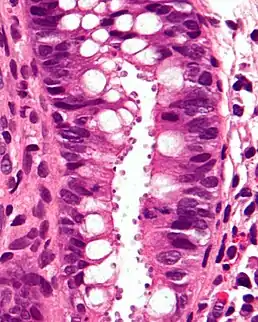

![]() Біоптат кишечнику при криптоспоридіозі, у просвіті видно мікроорганізми. Фарбування гематоксилин-еозином | ||

Збудник — дрібні кокцидії Cryptosporidium oocystes (родина Cryptosporiidae, підпорядок Eimeriina), що паразитують у поверхневому шарі епітелію слизової оболонки шлунка, товстої і тонкої кишок людини, різних тварин і птахів. Організм вперше був описаний в 1907 році Ернестом Е. Тайззером, який визначив його приналежність до кокцидій[3]. В ураженому організмі одночасно відбуваються статевий і безстатевий процес розвитку криптоспоридій. У довкіллі можуть зберігати життєздатність від 2 до 6 місяців. Хворобу у людей здатні спричинити 15 видів роду Cryptosporidium. Серед них більшість випадків пов'язана з Cryptosporidium hominis, для якого людина є єдиним природним господарем. Серед зоонозних видів велику частку уражень людей спричинюють C. parvum.